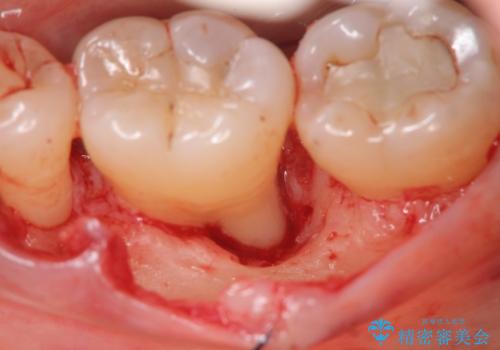

歯周病 再生治療で歯を残す

- 妊娠中に歯周病を指摘・自覚され、出産後に歯周病治療を希望され来院されました。

X線検査、歯周組織検査より歯の周囲の骨が溶ける歯周病であることがわかりました。

歯を抜かずに残せるよう、再生療法・歯周ポケット除去手術を計画します。

再生治療を行うことで、吸収した骨を再生し歯を保存できることがあります。